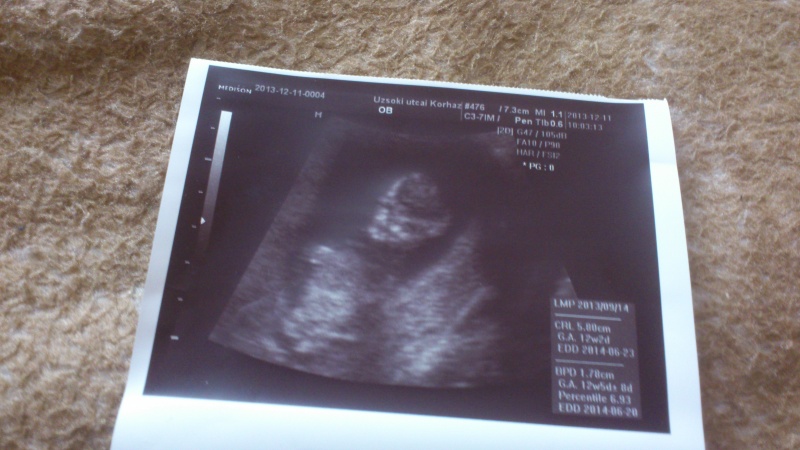

. Jók ezek az uh képek, minden baba kis csontváznak néz ki

Én mondjuk hallotam roszakat is az Uzsokiról mert annó nekem is szóba jött hisz az is közel van nekiünk, de ott azt hiszem 6 ágyas szobák vannak ami nekem nem jönne be... Én azért is választottam a honvédot mert ott csak 3 ágyas szobák vannak és az is mostmár 6 éve lett felújítva igaz ami megáltszik rajta, de így is nagyon szép és fantasztikus emberek dolgoznak az osztályokon!